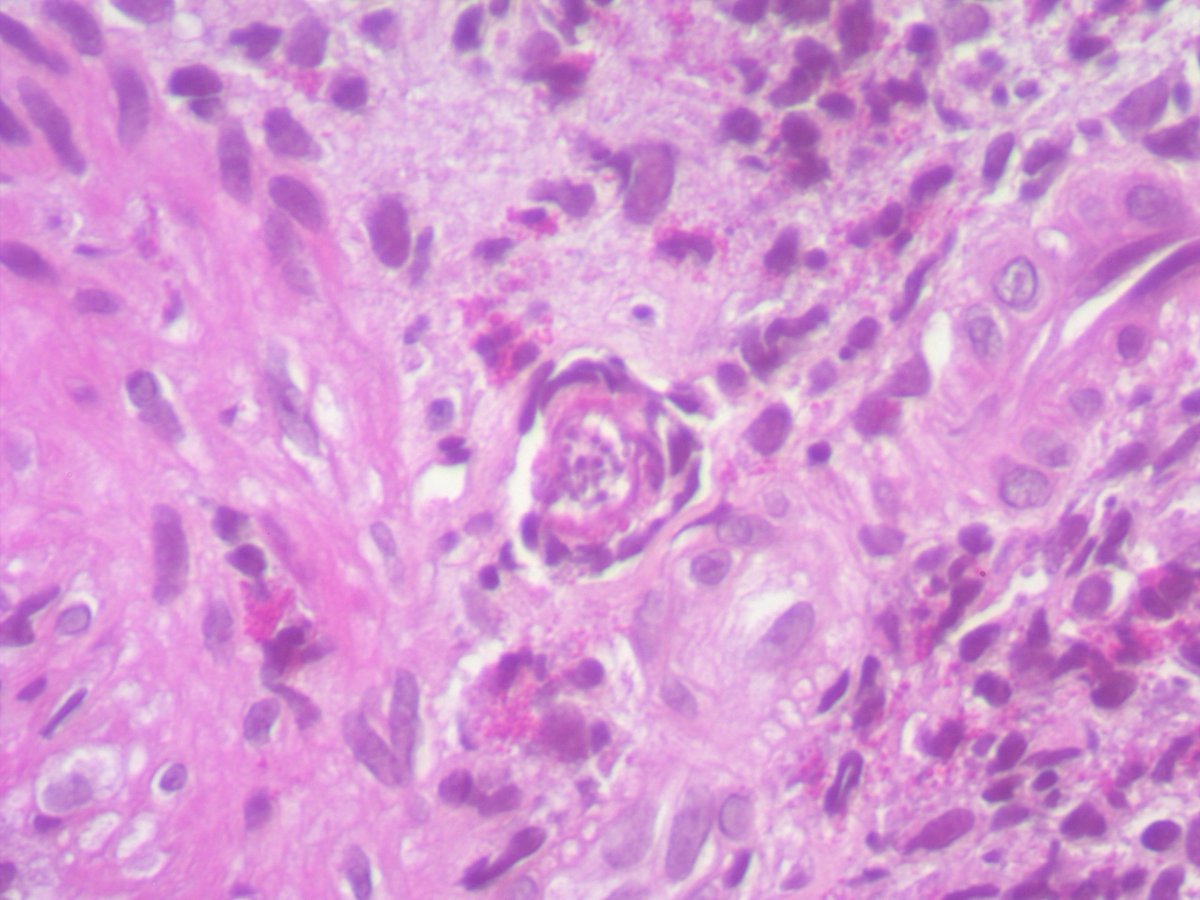

Any thoughts on this beautiful, elegant creature that "crawled" into the colonic mucosa and presented as polyp !! I have been googling it for ages and can't find a morphologic fit with any of the adult/ larval parasitic forms that I have ever encountered. Pt is asymptomatic.